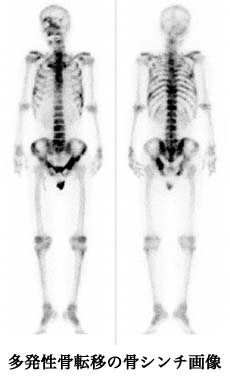

上記2種類のRI(放射性同位元素)は、骨の成分であるカルシウムと同じように骨に集まりやすい性質を持っているため、がんの骨転移の治療に適しています。これらのRI薬剤を注射し体内に送られると、代謝が活発になっている骨転移病巣に集まり、それぞれのRIから放出される放射線エネルギーにより、転移病巣を局所的に照射します。ストロンチウム-89は主にベータ線を放出し、ラジウム-223は主にアルファ線を放出するRIであり、それぞれ、エネルギーは強いのですが、物質を透過する力は弱く、患者様の体内から体外へ放出される放射線はごくわずかとなります。特に、RI検査である骨シンチグラフィにおいて、疼痛に一致した部位にRI集積が多い場合に、ストロンチウム-89もラジウム-223も集積が多くなる傾向にあります。

- 骨シンチで疼痛に一致する部位に集積増加がある場合